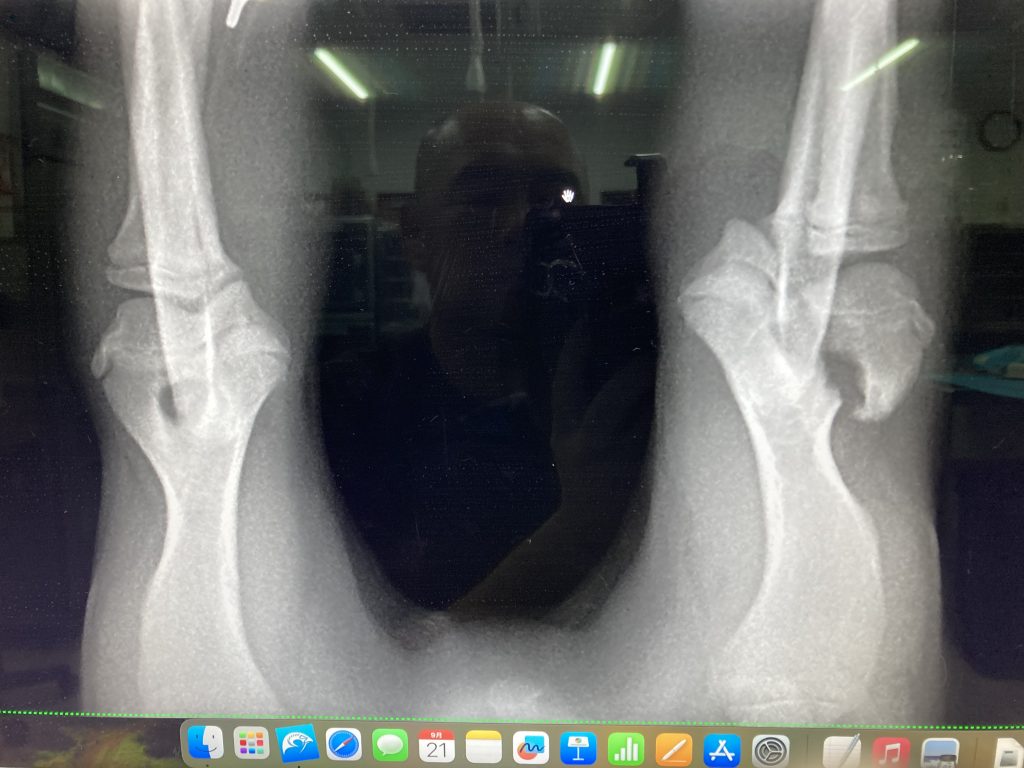

暫定診断:爪の腫瘍

レントゲン検査では爪の骨が溶解していました